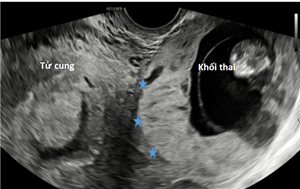

Thai lạc chỗ ở gan (TOG) là một thể không thường gặp của thai trong ổ bụng (TTOB)

Xem thêm